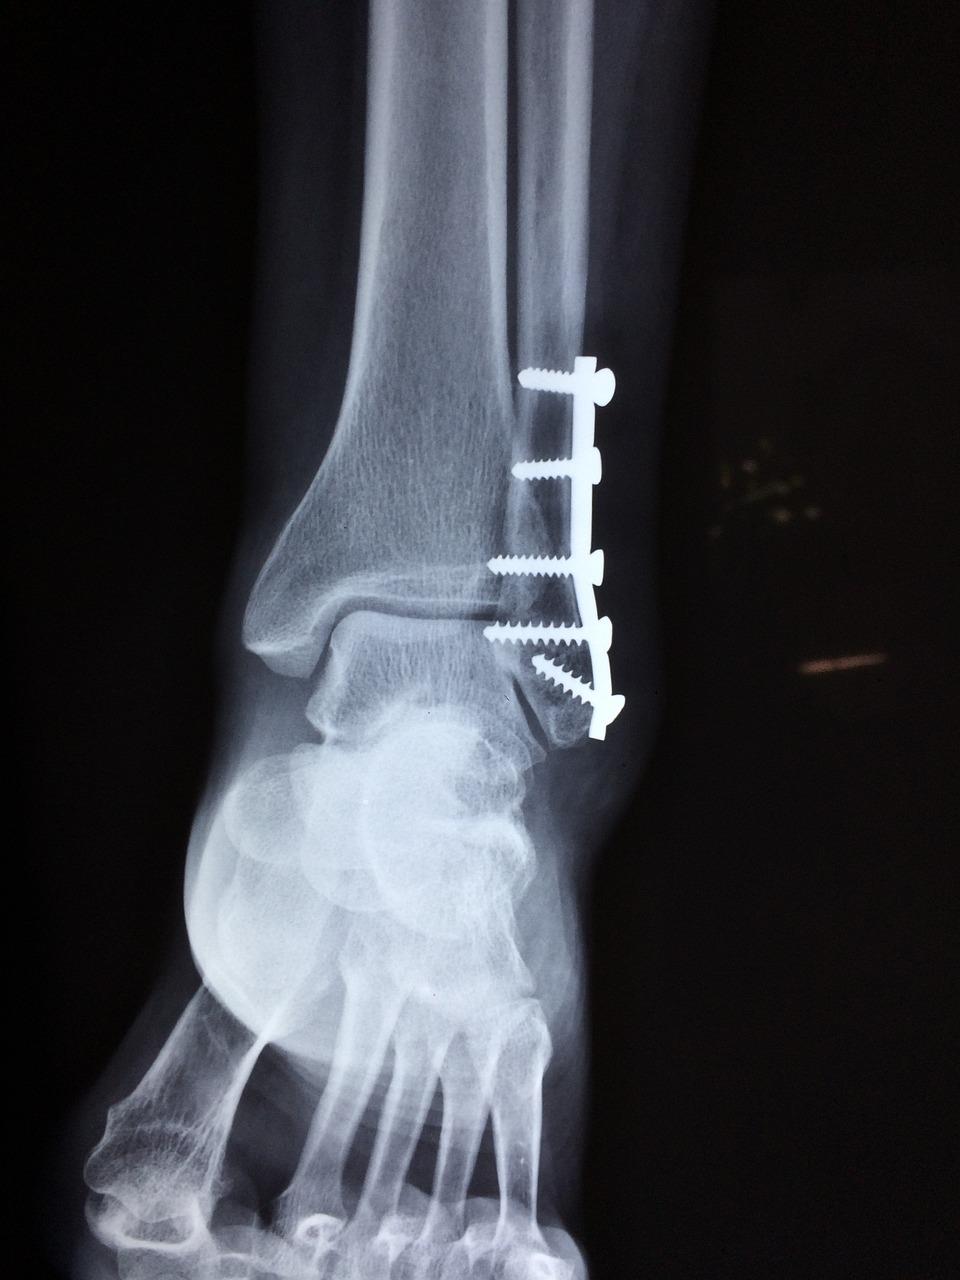

Orthopedische chirurgie is een belangrijk onderdeel van de zorg in Eindhoven. Van gewrichtsvervangende operaties tot complexe wervelkolomchirurgie, de specialisten in deze stad zijn bedreven in een verscheidenheid aan chirurgische ingrepen. Deze procedures worden ondersteund door geavanceerde technologieën zoals robotische assistentie en minimaal invasieve technieken, wat resulteert in snellere hersteltijden en betere resultaten voor patiënten.